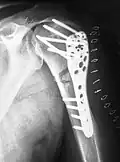

Als extramedulläre Operationsverfahren kommen hauptsächlich Plattenosteosynthesen und der Fixateur externe zur Anwendung. Bei besonderen Bruchformen, insbesondere bei sehr gelenknahen Brüchen, kommen seit den 1990er Jahren auch winkelstabile Platten zum Einsatz.

Eine Ausnahme sind distale und proximale Schaftfrakturen, die aufgrund der Hebelverhältnisse eine sichere Verriegelung eines Nagels nicht zulassen. Im distalen Bereich wird die Plattenosteosynthese daher weiterhin eingesetzt, im proximalen Bereich kommen seit den 1990er Jahren zunehmend winkelstabile Titanplatten zum Einsatz.